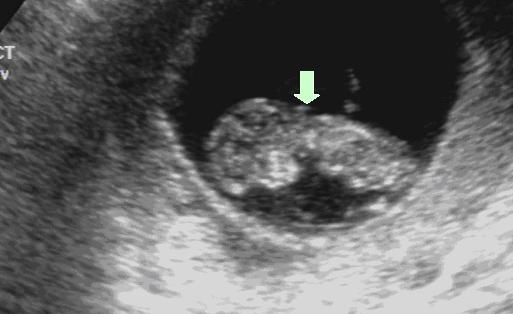

图1:NT正常的胎儿(箭头所指处即为NT) 图2:NT增厚的胎儿(箭头所指处即为NT)

图3:NT正常的胎儿(箭头所指处即为NT) 图4:NT增厚的胎儿(箭头所指处即为NT)